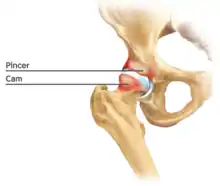

Figure 6. Diagram of the bony pathology of both cam and pincer impingement

Femoroacetabular impingement (see fig. 6)

Cam impingement is created by the abnormal development of the femoral head-neck junction causing what has previously been described as a 'pistol-grip deformity'. This type of deformity is characterised by varying amounts of abnormal bone on the anterior and superior femoral neck at the head-neck junction (see fig. 6). The head-neck junction is at the base of the ball of the hip, where it joins the short neck, which in turn carries on downwards into the femur, or thighbone, itself. A bony protrusion or bump at the head-neck junction has been likened to a cam, an eccentric part of a rotating device. This leads to joint damage as a result of the non-spherical femoral head being forced into the acetabulum mainly with flexion and/or internal rotation. This may impart compression and shear forces to the articular cartilage, and may lead to labral tears and peeling away of the articular cartilage from the underlying bone, so-called cartilage delamination (see fig. 8).[9][10]